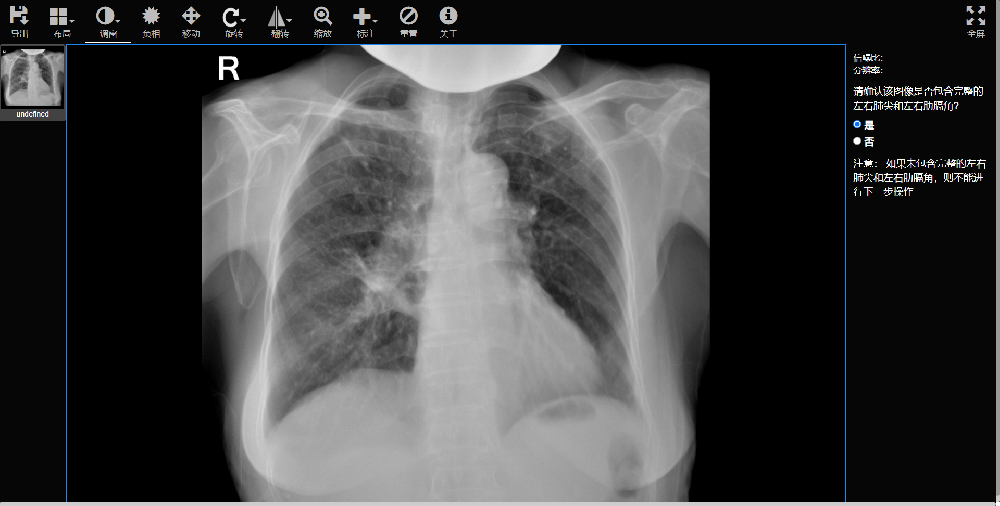

准确度:93

阈值50分的敏感度:91

阈值50分的特异度:94

AUC:0.97

肺结核X射线图像辅助评估软件